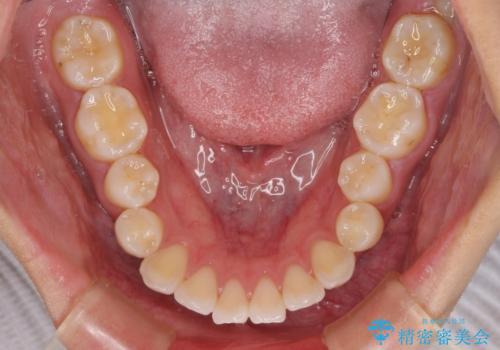

- 前歯が突出して、眠るときに口が開いてしまうことを気にして来院された患者様です。

横から見た際の口元の飛び出した印象も改善したいとのことで、上下左右の第一小臼歯4本を抜歯し、ワイヤー装置にて抜歯矯正を行うこととしました。

舌の突出癖改善のためのトレーニングをしっかりと実践してくださり、2年強の治療期間でしっかりと仕上げることができました。